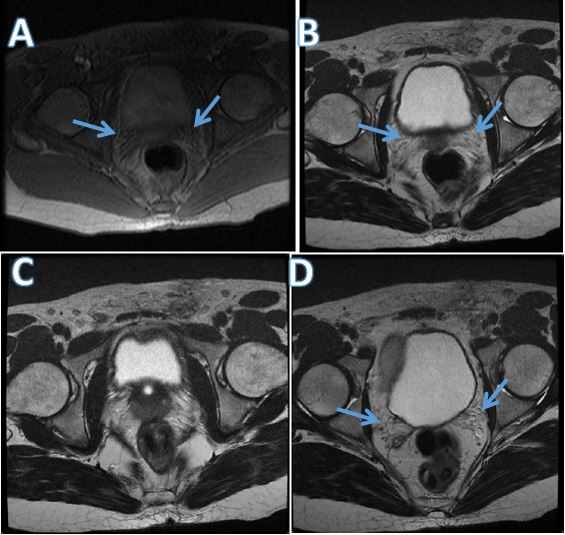

A 32-year-old patient. Obesity surgery operated at age 25 by By-pass with loss of about 30kgs, type 2 diabetes. Married for 5 years, he had regular and normal sexual intercourses with his 26-year-old companion who had a normal health check-up. Clinically there were no signs of hypogonadism, no urinary symptoms, no erectile dysfunction. The digital rectal examination did not record any abnormalities. Transrectal ultrasound revealed agenesis of a left seminal vesicle, hypotrophy of the right seminal vesicle, without individualization of vas deferens. Pelvic MRI noted an absence of bilateral vas deferens and agenesis of a left seminal vesicle and hypotrophy of the right seminal vesicle (Figure 1). Semen analyses were carried out and Absence of spermatozoa confirmed: volume 1ml, and pH of semen 7, 8 sperm concentration 0M/ml, vitality 0% and motility 0% (azoospermia).Hormonal assessment, FSH and inhibine were normal, normal testosterone. Constitutional karyotyping and search for microdeletions in the AZF regions of the Y chromosome were realized and noted no microdeletion in the AZF gene but the presence of an ACFTR mutation. Following these explorations we performed a microsurgical epididymal sperm aspiration (MESA) for an intracytoplasmic injection that was successfully carried out and allowed a paternity after the first attempt.

Figure 1 Pelvic MRI A, B, C noted an absence of bilateral vas deferens (CBAVD).

D agenesis of a left seminal vesicle and hypotrophy of the right seminal vesicle.